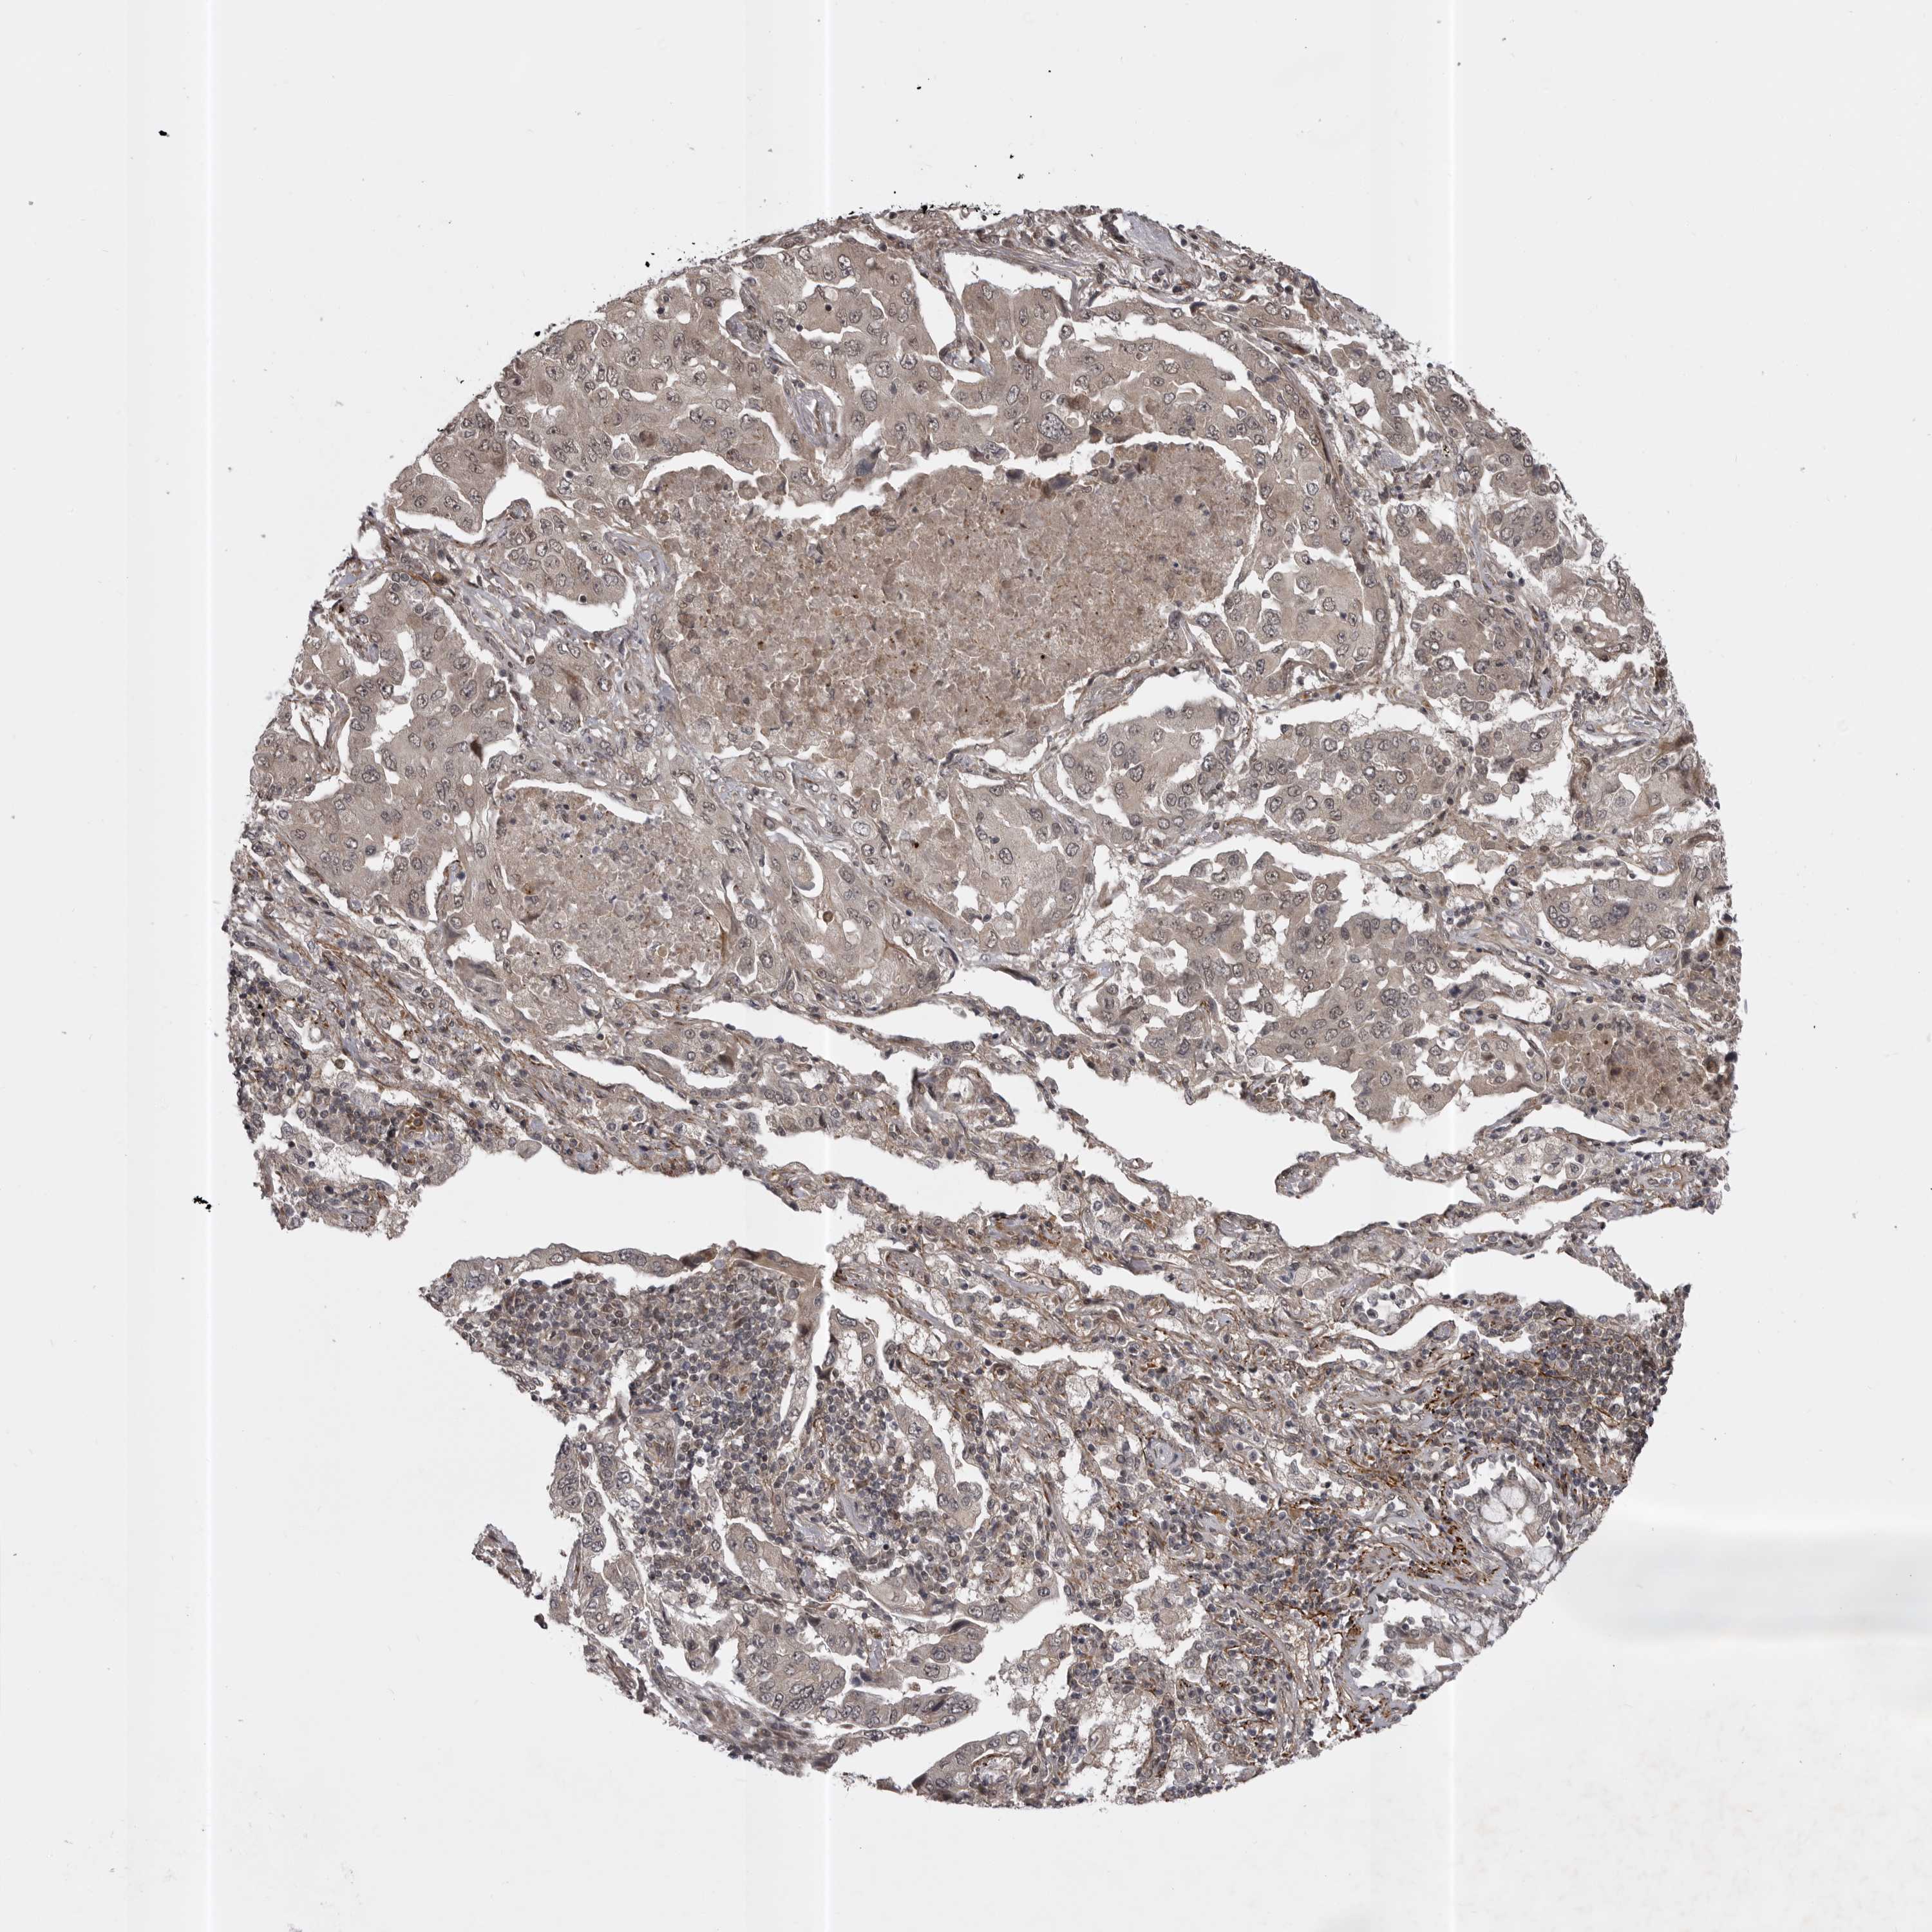

SNX16

LUNG ADENOCARCINOMA (VALIDATION) - Interactive survival scatter ploti

The Survival Scatter plot shows the clinical status (i.e. dead or alive) for all individuals in the patient cohort, based on the same data that underlies the corresponding Kaplan-Meier plots. Patients that are alive at last time for follow-up are shown in blue and patients who have died during the study are shown in red.

The x-axis shows the expression levels (FPKM) of the investigated gene in the tumor tissue at the time of diagnosis. The y-axis shows the follow-up time after diagnosis (years). Both axes are complimented with kernel density curves demonstrating the data density over the axes. The top density plot shows the expression levels (FPKM) distribution among dead (red) and alive patients (blue). The right density plot shows the data density of the survived years of dead patients with high and low expression levels respectively, stratified using the cutoff indicated by the vertical dashed line through the Survival Scatter plot. This cutoff is automatically defined based on the FPKM cutoff that minimizes the p-score. The cutoff can be changed by dragging the vertical line or by entering a cutoff value in the square labeled "Current cut-off".

Under the Survival Scatter plot the p-score landscape (black curve; left axis) is shown together with dead median separation (red curve; right axis). Dead median separation is the difference in median mRNA expression between patients who have died with high and low expression, respectively. It is calculated as follows: median FPKM expression of dead patients with high expression - median FPKM expression of dead patients with low expression. This is intended to aid the user in visually exploring custom cutoffs and the associated p-scores and dead median separation.

Individual patient data is displayed and can be filtered by clicking on one or more of the category buttons on the top of the page. Categories describing expression level and patient information include: high, low, alive, dead, female, male and tumor stages. The scale of the x-axis can be toggled between linear and log-scale by clicking on the "x log" button. Mouse-over function shows TCGA ID, patient information and mRNA expression (FPKM) for each patient.

& Survival analysisi

Kaplan-Meier plots summarize results from analysis of correlation between mRNA expression level and patient survival. Patients were divided based on level of expression into one of the two groups "low" (under cut off) or "high" (over cut off). X-axis shows time for survival (years) and y-axis shows the probability of survival, where 1.0 corresponds to 100 percent.

SNX16 is not prognostic in Lung Adenocarcinoma (validation)

Best expression cut offi

Based on the FPKM value of each gene, patients were classified into two groups and association between prognosis (survival) and gene expression (FPKM) was examined. The best expression cut-off refers the FPKM value that yields maximal difference with regard to survival between the two groups at the lowest log-rank P-value. Best expression cut-off was selected based on survival analysis .

When clicking on this number, the vertical dashed line indicating cut-off, the interactive survival plot, and the Kaplan-Meier curve will be adjusted to show results based on the best expression cut-off.

: 9.23

Median expressioni

Median expression refers to the median FPKM value calculated based on the gene expression (FPKM) data from all patients in this dataset. When clicking on this number, the vertical dashed line indicating cut-off, the interactive survival plot, and the Kaplan-Meier curve will be adjusted to show results based on the median expression.

: N/A

Median follow up timei

Median follow up time refers to the median time (years) after diagnosis with this type of cancer, based on clinical data from all patients in this dataset.

P scorei

Log-rank P value for Kaplan-Meier plot showing results from analysis of correlation between mRNA expression level and patient survival.

N/A

5-year survival highi

5-year survival for patients with higher expression than the expression cutoff.

For melanoma and glioma, 3-year survival is shown.

5-year survival lowi

5-year survival for patients with lower expression than the expression cutoff.

TCGA RNA samplesi

RNA-seq data is reported as average FPKM (number Fragments Per Kilobase of exon per Million reads), generated by the The Cancer Genome Atlas (TCGA) .

Normal distribution across the dataset is visualized with box plots, shown as median and 25th and 75th percentiles. Points are displayed as outliers if they are above or below 1.5 times the interquartile range. FPKM values of the individual samples are presented next to the box plot.

Average pTPM 11.9

Number of samples 105